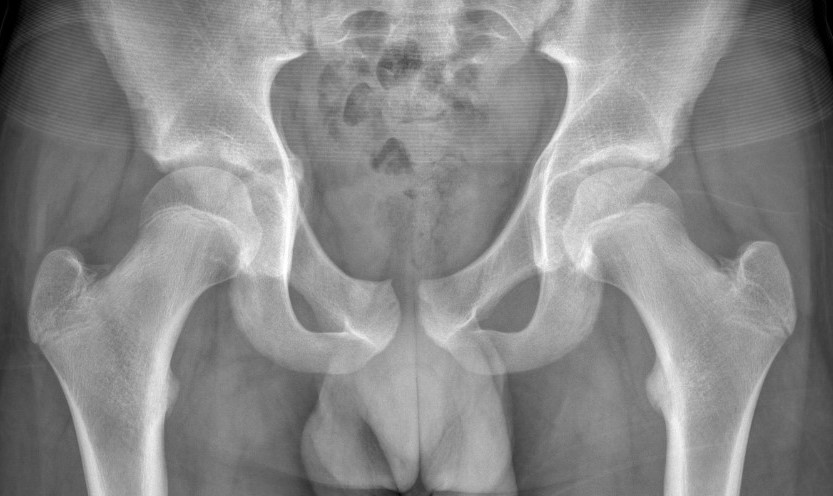

Classification Key & Conwell 1951

| No break in continuity of pelvic ring | Single break in ring | Double break in ring | Fracture of acetabulum |

A. Avulsion fractures 1. ASIS 2. AIIS 3. Ischial Tuberosity B. Fracture of pubis or ileum C. Fractured wing of ileum D. Fracture sacrum or coccyx |

A. Fracture of 2 ipsilateral pubic rami B. Fracture near or subluxation of symphysis pubis C. Fracture near or subluxation of SIJ |

A. Double vertical fractures or dislocation of pubis (straddle fracture) B. Double vertical fractures or dislocation (Malgaigne fracture) C. Severe multiple fractures |

A. Small fragment associated with dislocation of hip B. Linear fracture associated with non-displaced pelvic fracture C. Linear fracture associated with hip joint instability D. Fracture secondary to central dislocation |